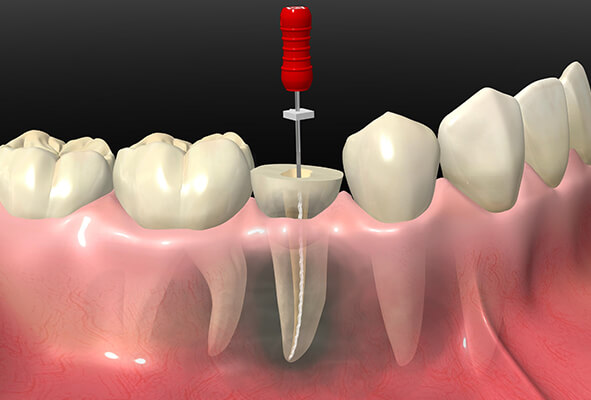

歯を抜かないための「根管治療」

「根管(こんかん)」とは、歯の神経が入っている細くて複雑な形状の管のことです。根管内が虫歯菌に感染してしまうと、激しい痛みが出るだけでなく歯が抜け落ちてしまうこともあります。根管治療では、歯を残すために根管内の感染した神経や歯質を除去し、消毒する処置を行います。

根管治療で注意すべき点は、感染した組織をわずかでも残さないように除去することです。万が一感染した組織が残ってしまうと、そこから再び感染が広がってしまう危険があります。そのため当院では、歯科用CTなどを駆使して安心・確実に治療を行っています。

ニッケルチタンファイル トライオートZX2

ニッケルチタン製ファイルは、患者様の根管の本来の形態を維持したまま、根管内をキレイにすることができる器具です。

しかし、ニッケルチタン製ファイルは治療中に急に折れてしまうことがありましたが、このトライオートZX2は回転する際のトルクを管理し、回転に変化を加えることにより、さらに折れにくく、簡単に、より安全に根管をキレイにすることができるようになりました。保険治療でも対応可能です。

【2】神経の除去

-

感染した神経を露出させて除去します。根管内は細く複雑な形状をしているため専用器具を使用します。

【3】根管の拡大

-

根管内に薬剤を詰めやすくするために、根管を削って拡大します。